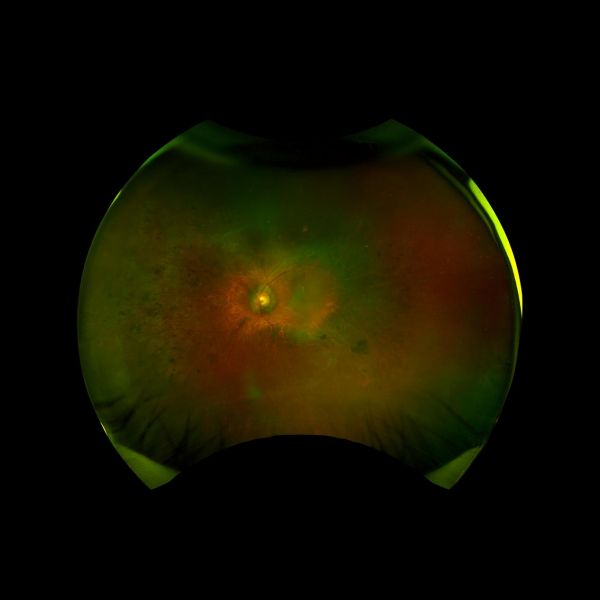

刘叔叔眼底照片量「眼」定制:刘红山院长精准施术破解难题

考虑到刘叔叔因视网膜色素变性导致视野受损,刘红山院长为其量「眼」定制手术方案,选用进光量更优、对比敏感度更高的艾无极单焦近视力改善型人工晶体,提升光线利用率与近距离视物清晰度,满足日常阅读与精细操作的需求。